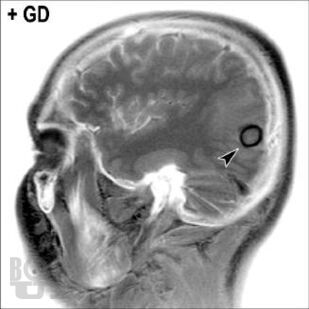

Книга «Опухоли мозга. КТ- и МРТ-диагностика» посвящена диагностике опухолевого поражения центральной нервной системы. При этом широко раскрыты особенности морфологической структуры каждой конкретной опухоли головного мозга. Структура изложения материала основана на классификации опухолей головного мозга по рекомендациям ВОЗ. Представленные опухоли в заголовке содержат шифр МКБ/О из 10-го пересмотра. Под каждым диагностическим изображением имеется подпись с обозначением его характеристик: метод исследования (КТ, МРТ, рентген, ПЭТ и др.), название ширины окна для КТ или импульсной последовательности на МРТ, а также ориентация среза в пространстве (аксиальный, сагиттальный или корональный). Данная особенность позволяет улучшить восприятие изображений, а также избежать путаницы при сопоставлении разных импульсных последовательностей и окон на МРТ и КТ.